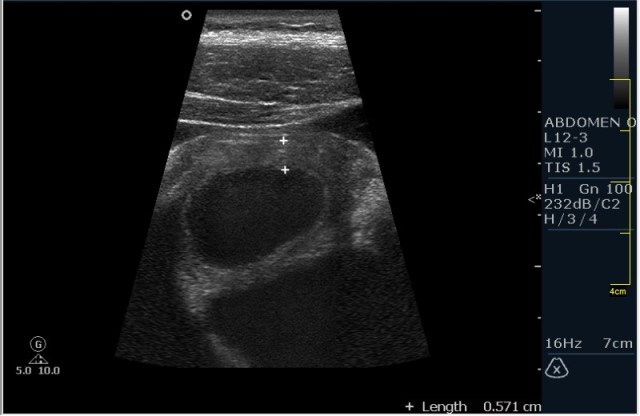

Мужчина 42 года; жалобы на периодические боли в эпигастрии. УЗИ области жёлчного пузыря выявило интересную картину; наблюдается фокальное утолщение стенок пузыря в области тела. Интересно узнать Ваше мнение?

В Желчном пузыре определялся мелкий конкремент и диффузное равномерное гипоэхогенное утолщение стенки на отграниченном участке, заключение морфологов-воспaлительный процесс (признаки холецистита).

Мне интерено, а почему Вы решили что это аденомиоматоз? На представленных сонограммах нет признаков этого заболевания, за исключением фокального утолщения стенки (что крайне не специфично, см. ниже). Если мы не находим пристеночных синусов (Ашоф -Ракитанского) образующихся за счёт неравномерной гиперплазии эпителия ЖП с протрузией эпителия в стенку, и не видим гиперэхогенные фокусы в стенке за счёт кристаллов холестерола; мы не можем выставлять диагноз аденомиоматоз. В нашем случае мы имеем дело с равномерным гипоэхогенным утолщением (см. сонограммы призведённые линейным датчиком с высоким разрешением).